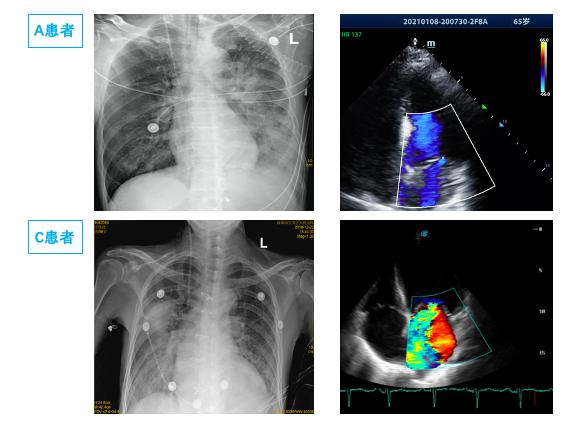

1.3 病例分组根据影像学表现分为双侧PE组和单侧PE组。单侧PE包括右侧和左侧PE(图 1图 2)。

| (A1、A2为同一患者,左侧PE,男,65岁,A1为发病前,A2为心脏骤停4 h后。B1、B2为同一患者,右侧PE,男,68岁,B1为心脏骤停后4 h后,B2为治疗3 d后。) 图 1 单侧肺水肿胸片表现 Fig 1 Manifestations of unilateral PE on X-ray |

2 结果通过病历系统回顾性分析2018年1月至2021年1月,共纳入314例患者,其中男性179例,女性135例,年龄18~97岁[(58.8±16.9)岁]。单侧PE患者共14例,发病率4.5%,男性10例,女性4例; 其中以右侧为主单侧PE 11例(78.5%),左侧PE患者3例(21.5%)。1例单侧PE呈右肺上叶局限性分布,(见图患者C),1例单侧PE以左下肺为主(见图患者A),其余单侧PE分布无明显肺段特点。

在本次试验中单侧PE发生率为4.5%,高于国外心内科单侧PE 2.1%发病率[2]。同时本次14例单侧PE中,主要(11例,78.5%)为右侧PE,与国外研究类似(16例,89%)[2]。本研究中,两组间左心室射血分数、左心房前后径、左心室舒张末内径等心脏超声参数均差异无统计学意义,与既往研究类似。同时该研究发现单侧PE患者重度二尖瓣反流比例高达100%[2]; 提示二尖瓣反流是导致单侧PE的主要原因。本研究中重度二尖瓣反流在单侧PE组发生率显著高于双侧PE组,35.7% vs 14.0%,但显著低于前述研究,可能与患者纳入标准有关,有5例(35.7%)因心室颤动等原因导致心脏骤停。其中如图 2中D患者,女,32岁,眼眶下局麻后心脏骤停。心脏骤停后3 hCT提示左肺弥漫渗出,但复苏8 h后查心脏超声无明显二尖瓣反流,考虑与心脏骤停冠脉缺血导致暂时性二尖瓣反流有关[25-26],因此24 h后复查CT左肺单侧PE完全消失。